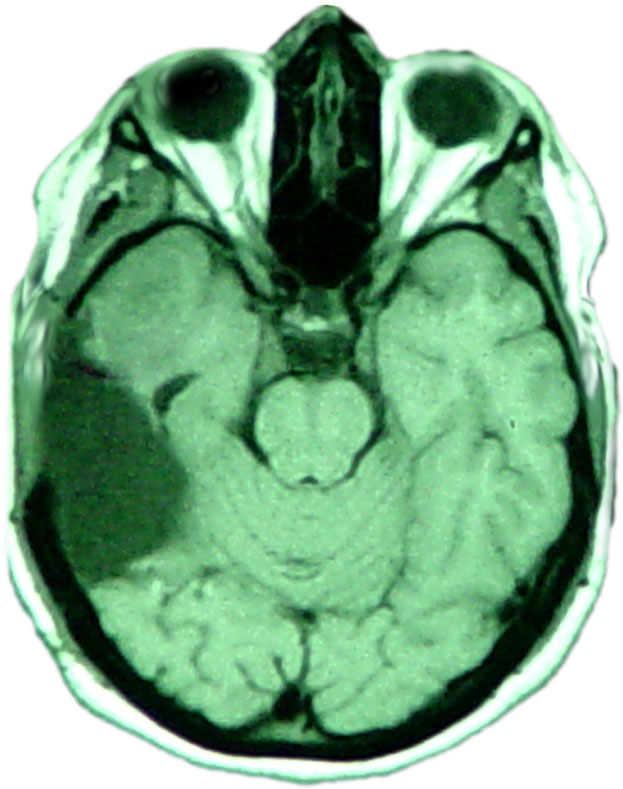

One of my customer's brain scan after softball size cancerous tumor was removed.